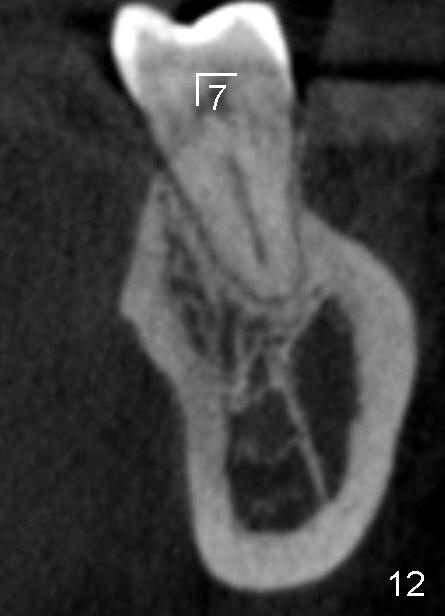

The submandibular (gland) fossa, or lingual (L) concavity (Fig.1 <), is more pronounced in the lower 2nd molar (7) that that of the first (6) (Fig.1 vs.2, 4 vs.3, the same patient). The lingual concavity may be mild (Type I, <2 mm depth, Fig.9-11), moderate (Type II, 2-3 mm, Fig.1,4, 12) and severe (Type III, >3 mm, Fig.13,14 (same patient)).